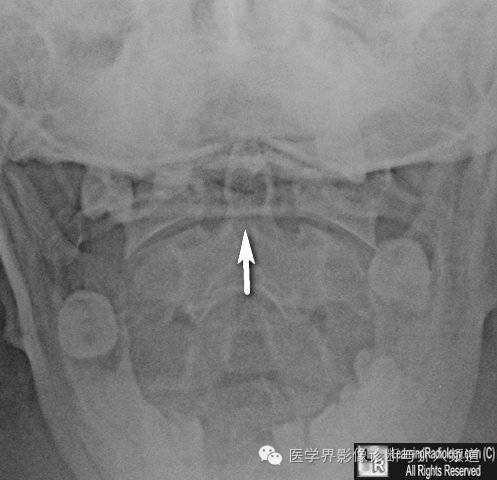

14、Mach线:Mach线是伪影的一种,表现为一黑线,常见于齿突基底部。